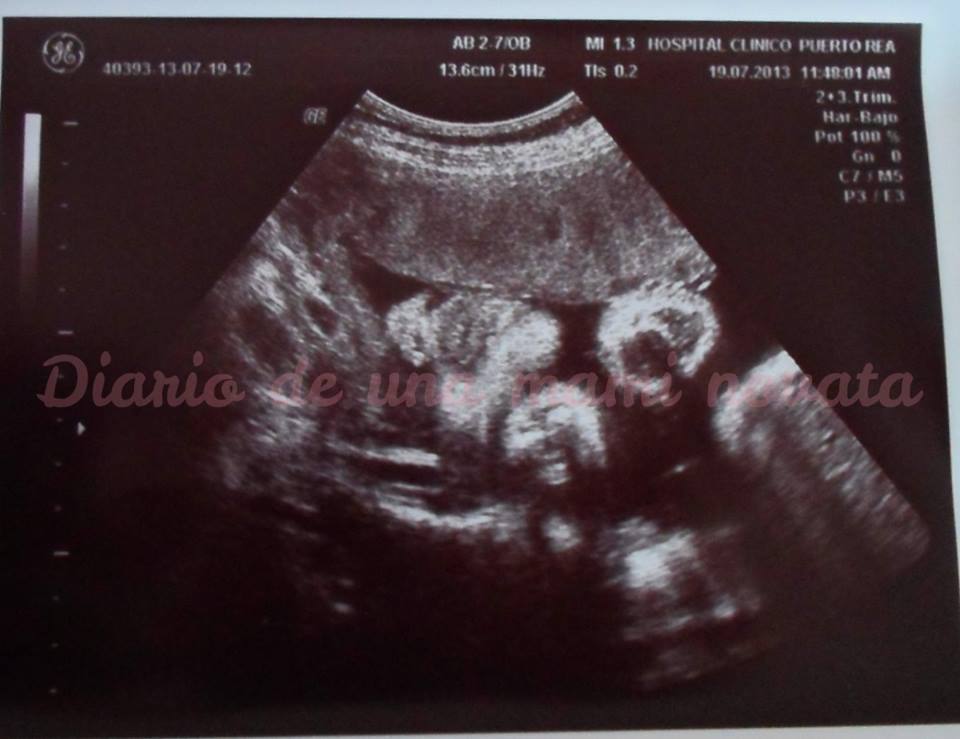

Llegamos al hospital y nos sentamos en la sala de espera, estaba petadisimo de embarazadas, unas con barriguita casi inexistente y otras que parecía que iban a reventar... para variar iba con retrasos las citas, yo entré sobre la 12:20 como muy temprano y aunque pensábamos que no iban a dejar entrar a dos acompañantes -mi abuela y Papá Pato- al final entramos los 3 a la eco, se vio todo PERFECTO, no pensé que en esta eco le viésemos con tanto detalle pero uff le vimos casi a la misma calidad que una 3D... los ojos, parpados, nariz con sus agujeritos, los labios, los mofletes y barbilla... chupándose la mano derecha... increíble, parecía casi que lo tenía delante -físicamente, me refiero- con esta eco ya hemos podido sacar parecidos, los labios son de Papá Pato pero los mofletones y nariz son míos.

Pesa 1,904Kg y mide sobre 44cm.